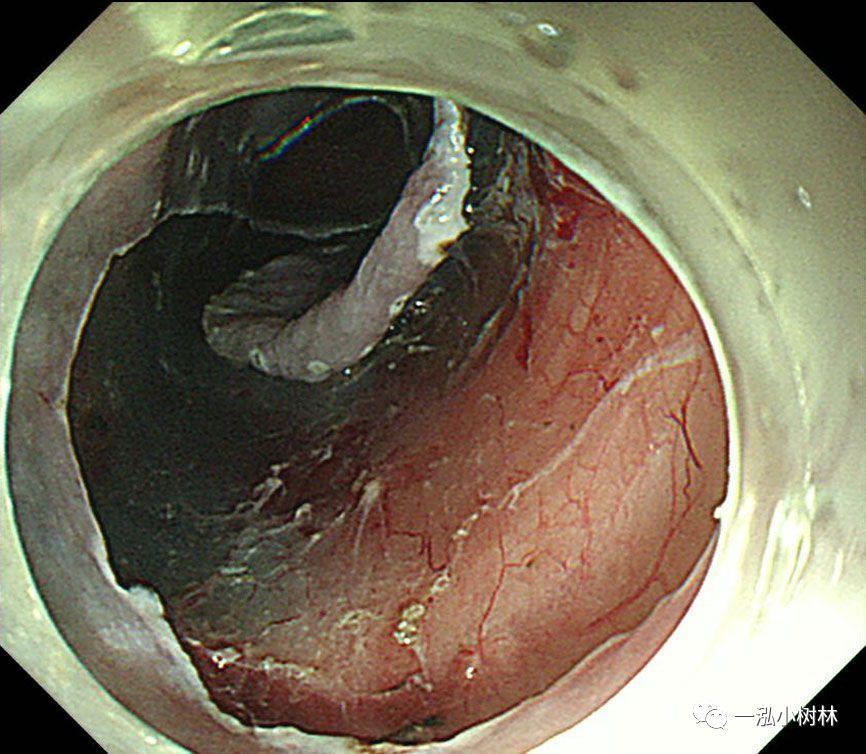

图8 行左侧黏膜下剥离术。在重力的作用下,黏膜剥离(左侧卧位行ESD)